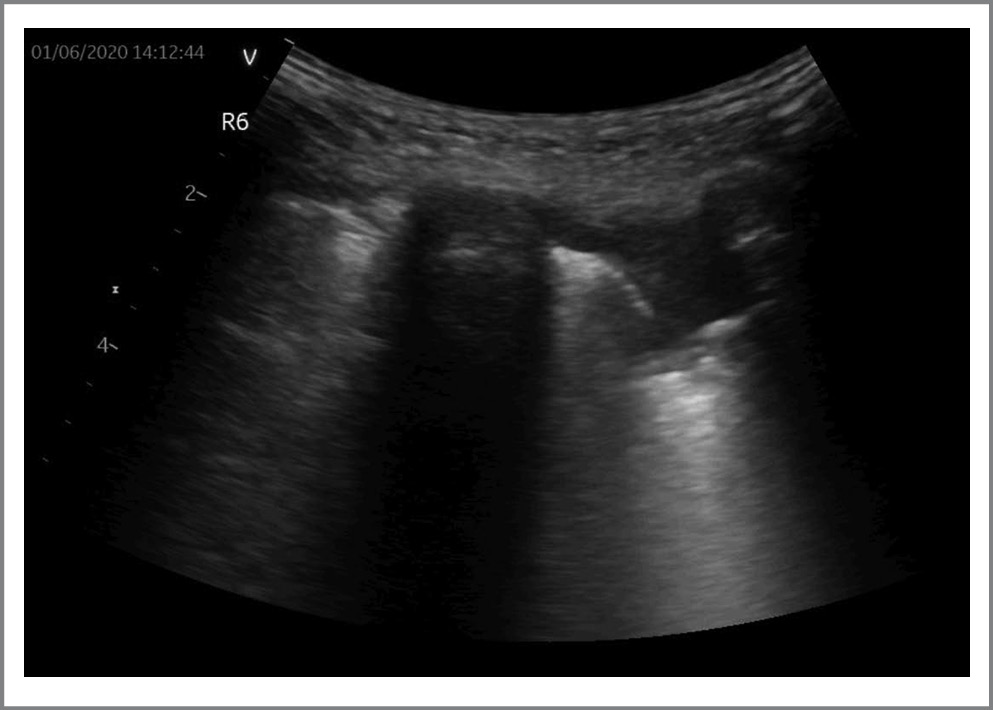

По данным УЗ-протокола у подавляющего большинства (n=33; 91,6%) пациентов прослеживались В-линии. У 26/36 (72,2%) пациентов выявлены патологические изменения в легких в виде участков консолидации (рис. 2). У 6/36 (16,6%) пациентов по данным УЗИ определялись изменения по типу «белое легкое», что соответствовало картине КТ-3–4 (рис. 3). Согласно данным литературы считается, что наличие консолидаций соответствует более тяжелому поражению легких по сравнению с множественными В-линиями [2, 8]. Однако мы, основываясь на собственном опыте, с учетом клинической картины, КТ-диаг- ностики и лабораторных данных отнесли изменения по типу сливных В-линий – «белого легкого» – к наиболее тяжелым поражениям у пациентов с COVID-19. Также к наиболее тяжелому поражению легких можно отнести сочетание отсутствия аэрации («белое легкое») с транслобарными консолидациями и аэробронхограммами.

У небольшого числа (11,1%) пациентов на УЗИ легких определялись такие признаки, как гепатизация, аэробронхограммы и признак «стратосферы»/штрих-код».